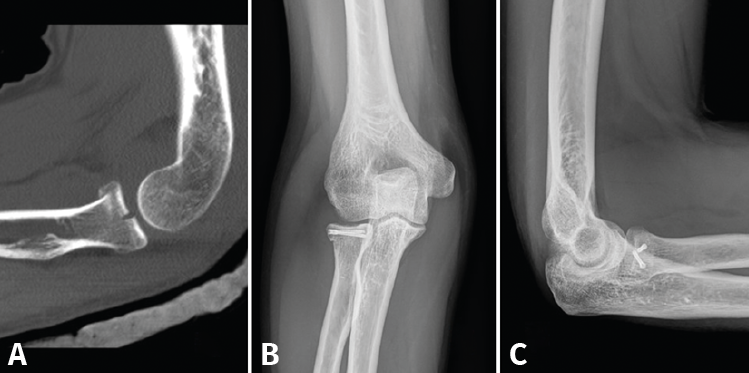

- Reducción abierta y fijación interna (RAFI): el objetivo es obtener una fijación anatómica y estable. Usaremos tornillos canulados de minifragmentos a compresión, sin cabeza, que dejaremos a nivel subcondral (Figura 3). Si existe afectación del cuello, lo ideal es sintetizar primero los fragmentos de la cabeza y añadir después algún tornillo hacia la diáfisis o una placa de bajo perfil (Figura 4)(13).

Figura 3. Ejemplo de fractura de Mason II tratada con 2 tornillos de minifragmentos canulados. A: imagen sagital en tomografía axial computarizada (TAC); B y C: radiografía anteroposterior y lateral de control a los 6 meses.